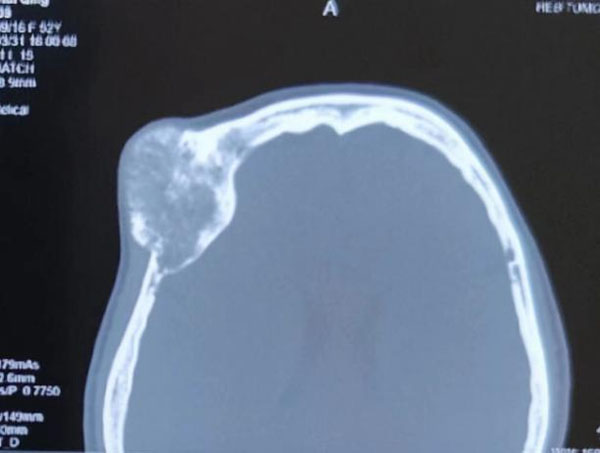

眼科。眼科郝玉华教授在检查中发现,患者右眼视力极低,右眼上睑下垂,眼球突出且运动明显受限。眼眶CT提示眶内巨大占位,几乎占据球后整个眶间隙。同侧额部颅骨骨质亦显示巨大肿瘤,约7*7 cm大小。患者已经有上睑下垂和视力明显下降的症状,表明肿物已经对眶上裂神经和视神经有一定压迫。

患者眶内肿瘤巨大,与众多神经血管相连,要求术者不能损伤眼球和血管神经,需将肿瘤等病变拿出后,再把组织修复。而且,患者合并全身系统性红斑狼疮和狼疮性肾炎,平素服用激素治疗,开眶、颅骨切除及复位后同时存在术后伤口愈合困难、坏死及术后易感染的风险,手术整体难度大。

针对眶内肿瘤与颅骨肿瘤是否同源,是否需要将两部位的肿瘤同时切掉,颅骨肿瘤距离外侧眶缘较近,完整切除颅骨肿瘤后,是否会对外侧开眶造成干扰等问题,结合患者自身情况,眼科会同多科室医务人员开展联合会诊,全面评估患者情况,制定详细手术方案,向患者及家属交代手术风险并得到家属同意。手术当日,眼科郝玉华教授、魏广川主任医师带领团队联合神经外科刘英姿主任医师,顺利完整切除患者眼眶内巨大肿瘤和颅骨巨大肿瘤,患者术后恢复良好,取得满意疗效。术后病理回报:右眼眶内海绵状血管瘤,右颅骨海绵状血管瘤,骨组织内可见血管瘤样增生。